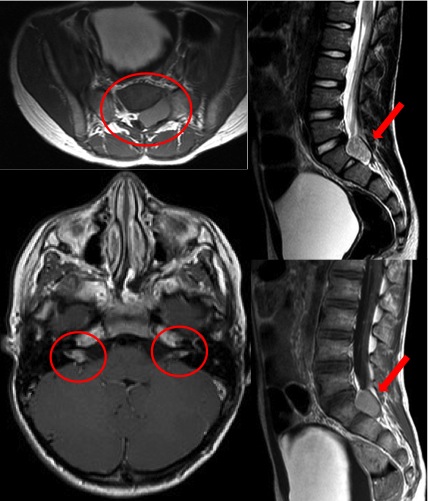

Figura. Immagini di RM del paziente alla diagnosi di NF2.

a. Sequenza assiale del rachide, pesata in T1 con gadolinio, che evidenzia una lesione spinale espansiva a sede intra- ed extrarachidea sinistra.

b-c. Sequenze sagittali del rachide (rispettivamente pesate in T2 e in T1 con gadolinio) che documentano la medesima lesione espansiva localizzata tra S1 e S2 e caratterizzata da omogeneo enhancement dopo mezzo di contrasto. Lesioni simili di dimensioni variabili (le maggiori con diametro trasverso di circa 3,5 cm) si sono riscontrate ubiquitariamente lungo il decorso di altre radici nervose.

d. Sequenza assiale dell�encefalo, pesata in T1 con gadolinio; nei canali acustici interni si apprezzano aree di alterazione del segnale con impregnazione contrastografica riferibili a neurinomi dell�VIII nervo cranico: questi non protrudono nella cisterna dell�angolo ponto-cerebellare n� ampliano il condotto uditivo interno.